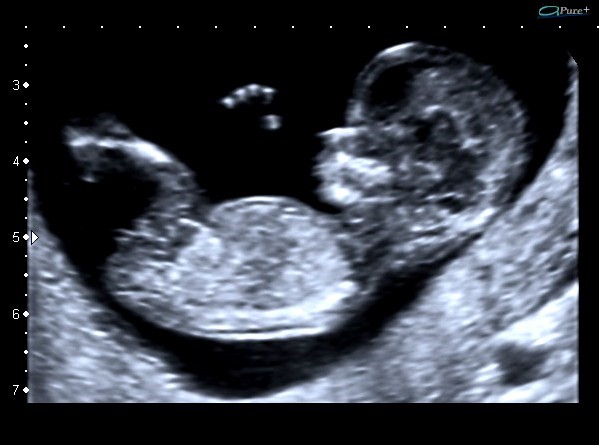

Ecografía de tamizaje genético: aunque puede realizarse entre las semanas 11 a 14, el mejor momento para hacer la ecografía de tamizaje genético es la semana 12. El tamaño actual del bebé permite determinar si la mayoría de órganos se estén desarrollando de manera adecuada. Esta ecografía en manos expertas puede detectar hasta el 60% de las malformaciones mayores que se pueden presentar durante el embarazo.

Uno de los parámetros más importante es la medición de la nuca del bebé conocida como translucencia nucal, que corresponde al líquido que todos los fetos tienen en la parte posterior del cuello. El grosor de la nuca del feto se utiliza para establecer el riesgo de síndrome de Down. Para calcular este riesgo se combina la medida de la nuca con tu edad, la presencia de soplo en el corazón, la forma en que palpita una vena que llega al corazón conocida como ductus venoso y los valores de dos hormonas (BHCG y PAPP-A) que se obtienen mediante una muestra de tu sangre.

Esta ecografía también permite establecer el riesgo de otras posibles complicaciones del embarazo como el parto prematuro, la preeclampsia (presión alta durante el embarazo) y la restricción del crecimiento fetal (bajo peso del bebe durante la gestación). En caso de identificar alto riesgo de preeclampsia tu médico te formulará 150 mg de ácido acetil salicílico cada noche y calcio para disminuir la probabilidad de que esto ocurra.